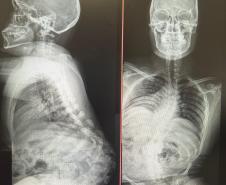

Aos 14 anos, a adolescente Milena de Andrade Carvalho, moradora de Guaratuba, no Litoral do Estado, foi diagnosticada com escoliose idiopática. Sem causa definida, esse tipo de escoliose pode surgir a partir dos quatro anos até a adolescência e ocorre durante o estirão de crescimento. Quando a condição da curvatura ultrapassa os 40 graus, a escoliose se torna progressiva e o paciente continua entortando. Essa condição ocorre com maior frequência em meninas e é muito importante que os pais estejam atentos a qualquer sinal do problema.

“Descobrimos a escoliose por acaso, nunca tínhamos percebido a deformidade, até que um dia ao amarrar meu biquíni, minha mãe observou que eu estava com a coluna torta e ao passar a mão percebeu a curvatura. Decidimos então procurar atendimento médico e tive o diagnóstico da doença já com 50 graus de curvatura e indicação imediata de cirurgia”, contou a adolescente.